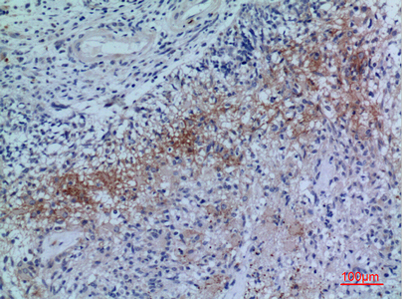

| Product name: | Neuropilin-2 rabbit pAb |

| Dilutions: | Western Blot: 1/500 - 1/2000. IHC-p: 1:100-300 ELISA: 1/20000. Not yet tested in other applications. |